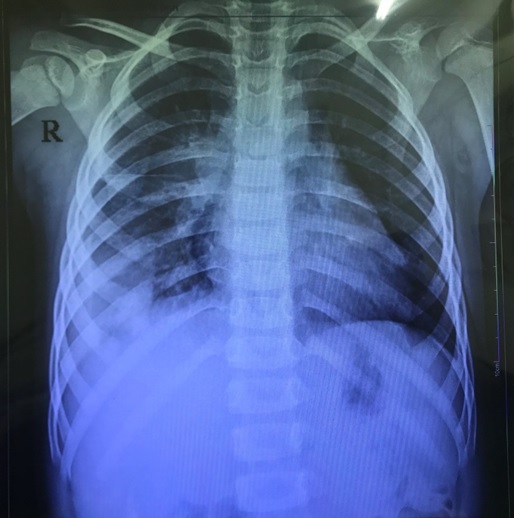

Hình ảnh Xquang phổi của bệnh nhân mắc viêm mủ màng phổi

Chụp X quang phổi thẳng và nghiêng thấy hình ảnh góc sườn hoành bị tù (mờ nhiều hay ít tuỳ mức độ tràn dịch) hoặc hình ảnh vách hoá khoang màng phổi. Siêu âm khoang màng phổi thấy hình ảnh tràn dịch toàn bộ hay vách hoá tạo thành ổ cặn.